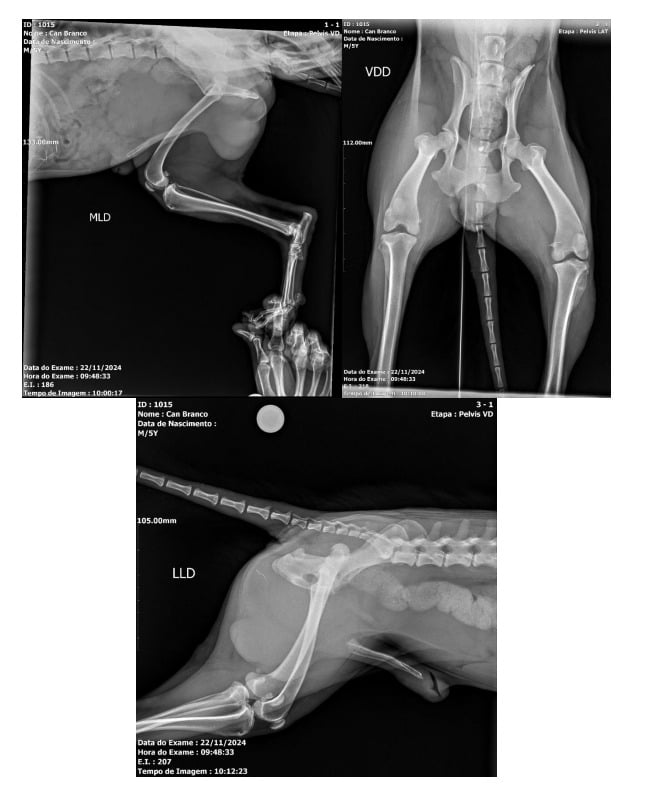

O animal foi socorrido pelo Maycon, que tem uma oficina na rua que aconteceu o atropelamento, e deve passar por cirurgia ortopédica nesta segunda-feira (25). Segundo Maycon, o motorista se nega a custear o tratamento ou ajudar de alguma forma.

Maycon fez uma vaquinha para custear a internação e cirurgia, evitando que o animal sofresse na rua sem amparo. O valor total na clínica veterinária é de R$ 5.700,00.

Na descrição da vaquinha virtual, Maycon diz que o cachorro é dócil e era alimentado em sua oficina. “Já deu 4 mil reais a cirurgia mais internação, raio x e medicações, e após a cirurgia vai precisar ficar mais uns 10 dias internado pra se recuperar! E esse gasto tá saindo totalmente do meu bolso! Então quem quiser ajudar o cachorro eu ficarei muito feliz”.